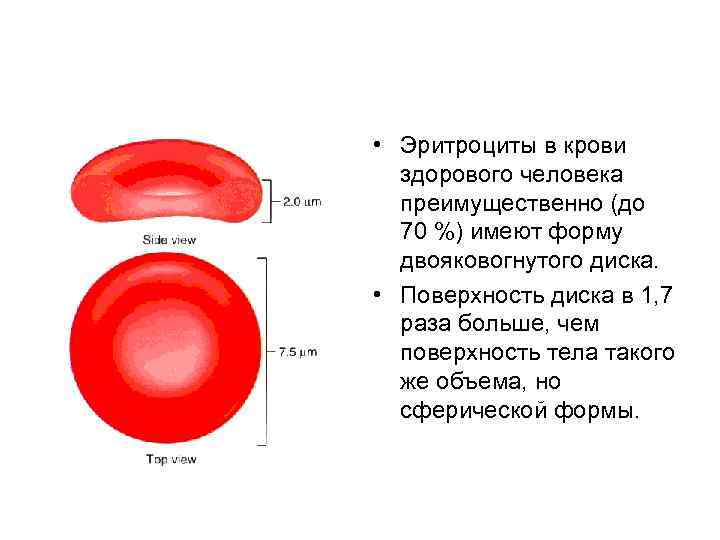

• Эритроциты в крови здорового человека преимущественно (до 70 %) имеют форму двояковогнутого диска. • Поверхность диска в 1, 7 раза больше, чем поверхность тела такого же объема, но сферической формы.

• Эритроциты в крови здорового человека преимущественно (до 70 %) имеют форму двояковогнутого диска. • Поверхность диска в 1, 7 раза больше, чем поверхность тела такого же объема, но сферической формы.

В зависимости от диаметра выделяют следующие эритроциты: • • 6 -9 мкм – нормоциты менее 6 мкм - микроцитами более 9 мкм – макроцитами более 12 мкм – мегалоциты.

В зависимости от диаметра выделяют следующие эритроциты: • • 6 -9 мкм – нормоциты менее 6 мкм - микроцитами более 9 мкм – макроцитами более 12 мкм – мегалоциты.